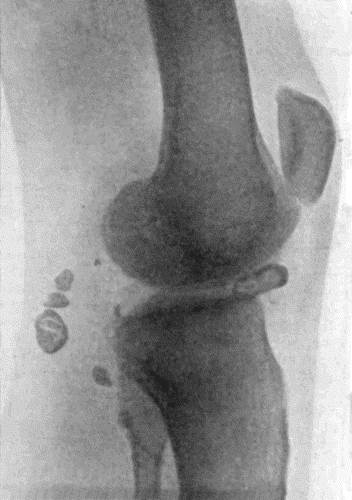

138.Radiogram of Right Knee showing Multiple Exostoses 482

139.Multiple Exostoses of Limbs 483

143.Skiagram of Multiple Chondromas 489